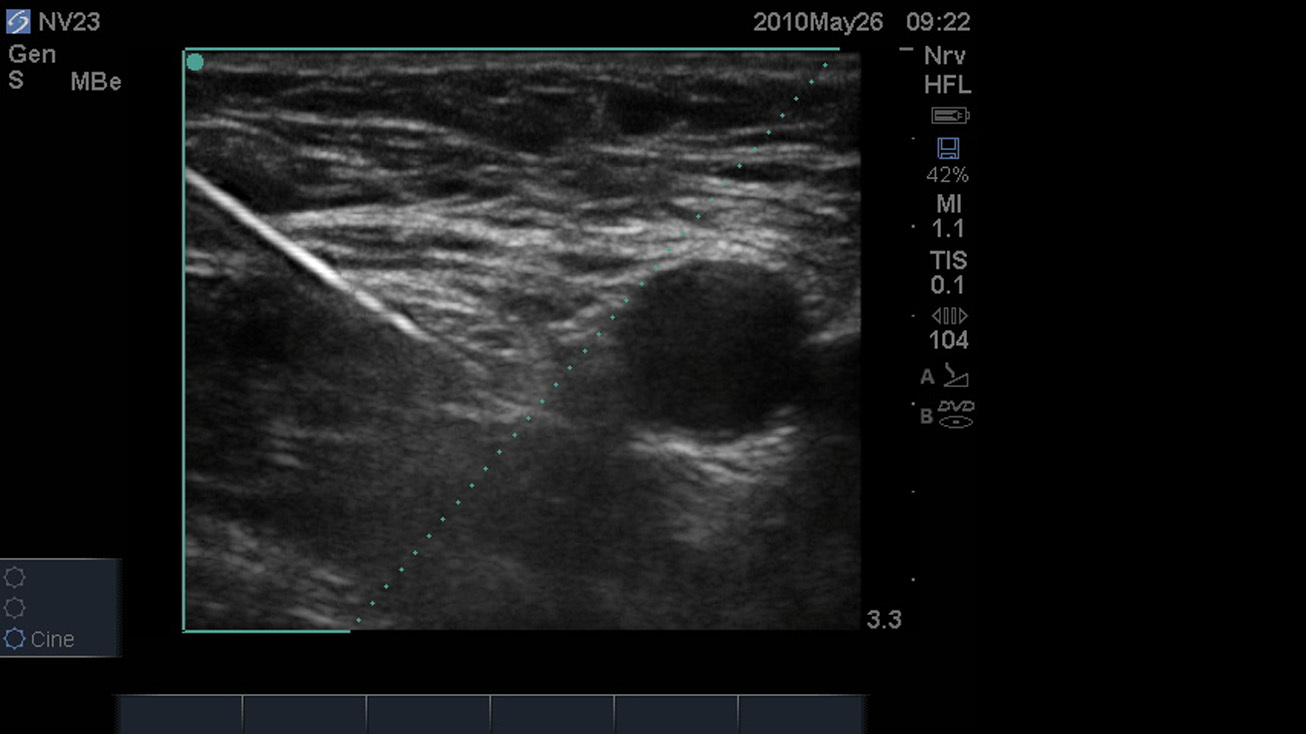

SonoMBe オン– 急大腿神経3cm 画像